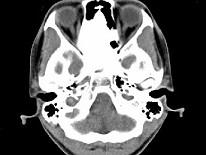

问题 女,17岁,鼻阻塞、头痛两年.如图所示符合筛骨病变最可能的诊断是 ( )

选项 A、骨瘤 B、骨化性纤维瘤 C、纤维异常增殖症 D、软骨瘤 E、成骨肉瘤

答案 B